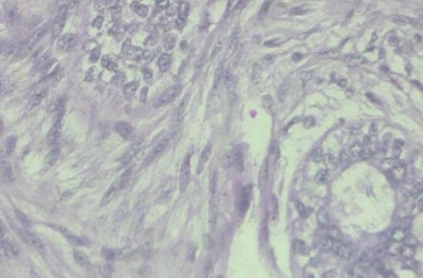

Background: Breast cancer has the highest prevalence in women globally. The classification and diagnosis of breast cancer and its histopathological images have always been a hot spot of clinical concern. In Computer-Aided Diagnosis (CAD), traditional classification models mostly use a single network to extract features, which has significant limitations. On the other hand, many networks are trained and optimized on patient-level datasets, ignoring the application of lower-level data labels. Method: This paper proposes a deep ensemble model based on image-level labels for the binary classification of benign and malignant lesions of breast histopathological images. First, the BreakHis dataset is randomly divided into a training, validation and test set. Then, data augmentation techniques are used to balance the number of benign and malignant samples. Thirdly, considering the performance of transfer learning and the complementarity between each network, VGG-16, Xception, Resnet-50, DenseNet-201 are selected as the base classifiers. Result: In the ensemble network model with accuracy as the weight, the image-level binary classification achieves an accuracy of $98.90\%$. In order to verify the capabilities of our method, the latest Transformer and Multilayer Perception (MLP) models have been experimentally compared on the same dataset. Our model wins with a $5\%-20\%$ advantage, emphasizing the ensemble model's far-reaching significance in classification tasks. Conclusion: This research focuses on improving the model's classification performance with an ensemble algorithm. Transfer learning plays an essential role in small datasets, improving training speed and accuracy. Our model has outperformed many existing approaches in accuracy, providing a method for the field of auxiliary medical diagnosis.